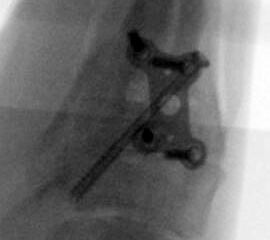

Es wird hier die Lapidusarthrodese mit Fixation durch eine medial angebrachte winkelstabile Platte in Kombination mit einer Zugschraube beschrieben 2. Durch diese Kombination läßt sich eine verglichen zur Schraubenosteosynthese hohe Primärstabilität erreichen, verbunden mit einem niedrigen Risiko einer Pseudarthrosenbildung 3.

Abbildung 15a

Abbildung 15b